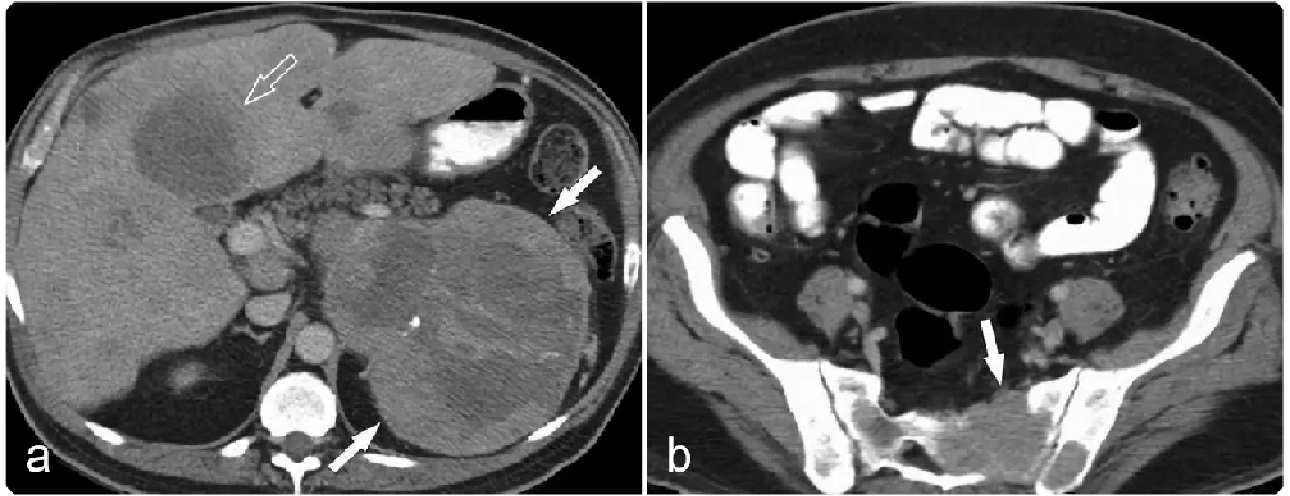

0a5fb18a3933294f8c258284440d05bf.png 病例 8:腹膜后(血管外)平滑肌肉瘤  46岁女性 腹膜后肿物不均质强化,病灶与前方下腔静脉、上方肾上腺及下方肾脏分界清晰,病灶侵犯右侧腰大肌。瘤内少量出血,不均质强化,弥散受限。大体病理显示瘤内出血、坏死;镜下:具有有丝分裂和核异型的梭形细胞。

0a6556b925dbc726a8c295b13d4e5389.png 病例 9:腹膜后(血管外)平滑肌肉瘤  64岁女性右侧腹膜后巨大软组织肿块,不均质强化侵犯肝脏(黑箭)及右肾(白箭)。大体病理显示肿瘤侵犯右肾,瘤内出血、坏死(*)。

5cda817c00c60fa04c459763294e72d0.png 病例 10:腹膜后(血管外)平滑肌肉瘤  66岁男性,腹痛3个月,食欲下降,体重减轻右肾周巨大不均质肿块,内见坏死区,未见侵犯右肾。大体病理显示肿瘤位于右肾下部,完全位于肾外,肿瘤切面呈棕白色轮辐状外观。